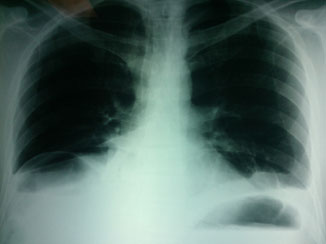

La tele de tórax mostró un hemidiafragma derecho elevado con nivel hidroaéreo, por lo que hubo sospecha de absceso pulmonar (figuras 3 y 4). Por lo tanto, se llevó a cabo una TAC de tórax en la que se observó una imagen redondeada con doble nivel hidroaéreo de aspecto tabicado, condensación basal derecha y derrame pleural, sin adenomegalias. El reporte de radiología fue de empiema derecho (figuras 5 y 6).